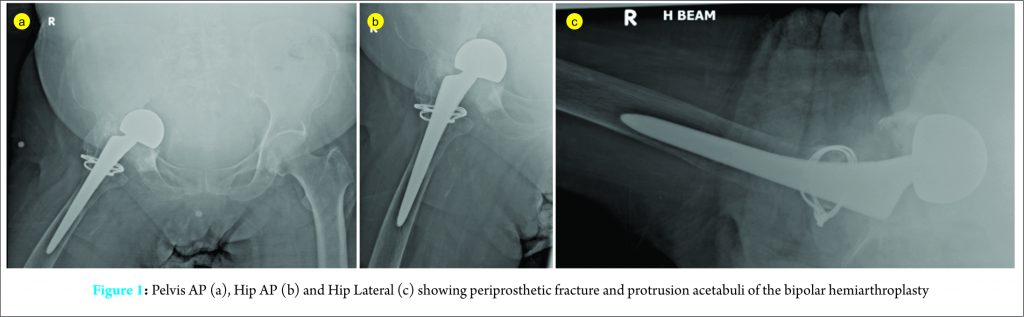

In 2009, a 60-year-old Asian woman presented with a displaced fracture of the neck of femur after a mechanical fall. She is a non-smoker and her co-morbidities include hypertension, non insulin-dependent diabetes mellitus, ischaemic heart disease and peripheral vascular disease. A right hip bipolar hemi-arthroplasty was performed and she recovered well post-operatively. She was later lost to follow-up after one year post-operatively. She was community ambulant with a walking frame 3 years post-operatively with intermittent right hip pain. 5 years later, she presented with right hip pain following a low velocity mechanical fall. Pelvic AP X-ray and right hip AP/lateral X-ray demonstrated grade III (Sotelo-Garza and Charnley 1978) severe acetabular prosthetic protrusion with peri-prosthetic fracture,causing loosening over the femoral stem implant, ( Fig. 1(a), (b) and (c)). Her C-reactive protein (CRP) was 21.7 milligram/litre and erythrocyte sedimentation rate (ESR)was 87mm/hour. CT angiogram showed a patent abdominal aorta and iliac arteries. The right common femoral artery travelling closest to the implant (within 8 mm at the 12 o’clock position) with no evidence of aneurysm or dissection noted. Aspiration of her right hip under fluoroscopic guidance was performed with negative culture and unremarkable histological findings with no malignant cells or significant acute inflammation. However, in view of the elevated inflammatory markers, there was significant concern for peri-prosthetic joint infection and the patient was counseled for a 2-stage revision arthroplasty.